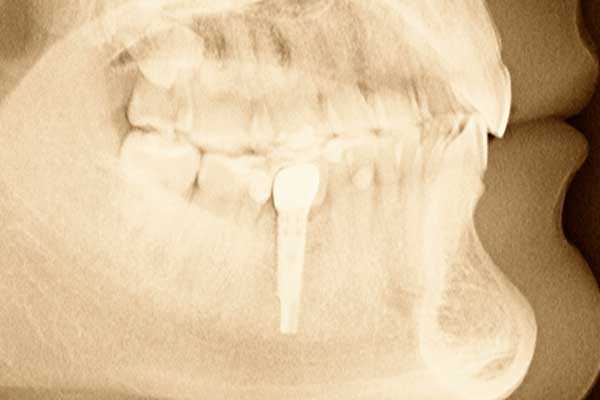

Dental implants replace tooth roots in the mouth. Implants provide a strong foundation for fixed or removable replacement teeth. Dental implants, which are placed in the jawbone, are small anchors made of a biocompatible metal called titanium. The anchors begin to fuse with the bone over the course of a few months. After the fusing process, known as osseointegration, abutment posts are inserted into the anchors to allow for the permanent attachment of the replacement teeth.